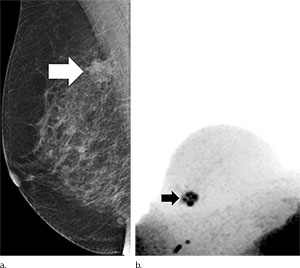

Sebastian Bickelhaupt, M.D., of the German Cancer Research Center, Heidelberg, Germany, and colleagues conducted a prospective institutional review that included 50 women (mean age, 57.1 years; range, 50-69 years), who gave informed consent and who had suspicious screening mammograms and an indication for biopsy from September 2014 to January 2015. Before biopsy, full diagnostic contrast-enhanced MR imaging was performed that included DWIBS (b = 1500 sec/mm2). Two abbreviated protocols (APs) based on maximum intensity projections (MIPs) were evaluated regarding the potential to exclude malignancy: DWIBS (AP1) and subtraction images from the first post-contrast and the unenhanced series (AP2). Diagnostic indexes of both methods were examined using the McNemar test and were compared with those of the full diagnostic protocol and histopathologic findings.

Of the 50 participants, 24 (48 percent) had a breast carcinoma. With AP1 (DWIBS), the sensitivity was 0.92 (95 percent confidence interval [CI]:0.73, 0.98), the specificity was 0.94 (95 percent CI: 0.77, 0.99), the negative predictive value (NPV) was 0.92 (95 percent CI: 0.75, 0.99), and the positive predictive value (PPV) was 0.93 (95 percent CI: 0.75, 0.99). The mean reading time was 29.7 seconds (range, 4.9–110.0 seconds) and was less than 3 seconds (range, 1.2–7.6 seconds) in the absence of suspicious findings on the DWIBS MIPs. With the AP2 protocol, the sensitivity was 0.85 (95 percent CI: 0.78, 0.95), the specificity was 0.90 (95 percent CI: 0.72, 0.97), the NPV was 0.87 (95 percent CI: 0.69, 0.95), the PPV was 0.89 (95 percent CI: 0.69, 0.97), and the mean reading time was 29.6 seconds (range, 6.0–100.0 seconds).

Unenhanced diagnostic MR imaging–DWIBS mammography achieved a comparable accuracy to the full diagnostic protocol and to abbreviated contrast-enhanced protocols when used as a complementary method after screening mammography, according to researchers.

“The comprehensive method is fast and robust to perform as a complement to routine mammography. Along with lack of need for intravenous contrast agent administration, ad-vantages include its short acquisition time of less than seven minutes and short reading time of less than 30 seconds,” the authors write.